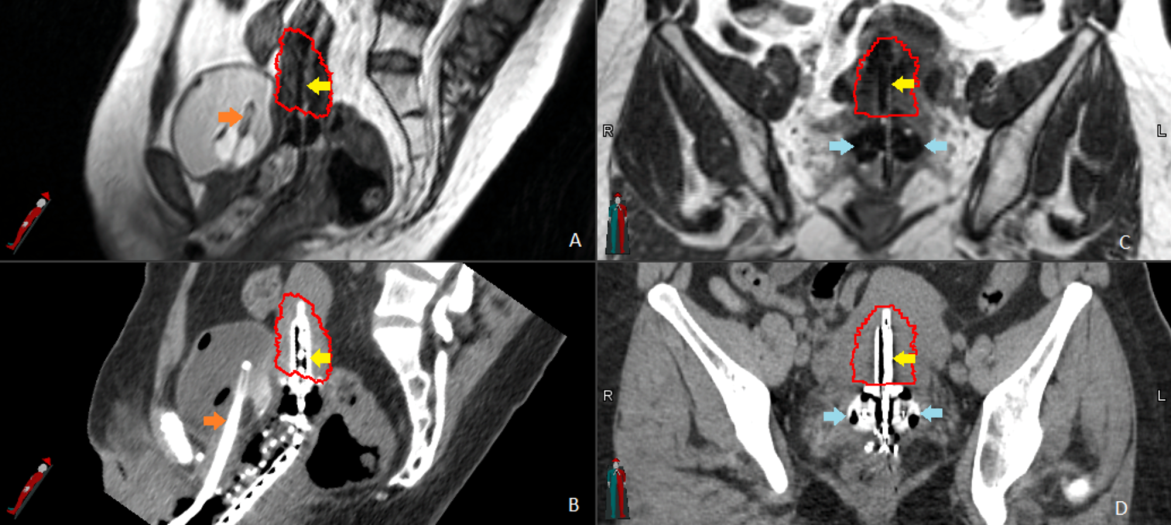

IMAGE GUIDED BRACHYTHERAPY(IGBT):

Image guided brachytherapy(IGBT) uses cross sectional image data to create 3D models.

IGBT is the use of advanced imaging technique to make brachytherapy more accurate and effective.

IGBT involves four phases:

1. Placement of hollow catheters / carriers

2. CT or MRI imaging

3. Computer calculation of dose distribution called dosimetry

4. Radiation treatment delivery